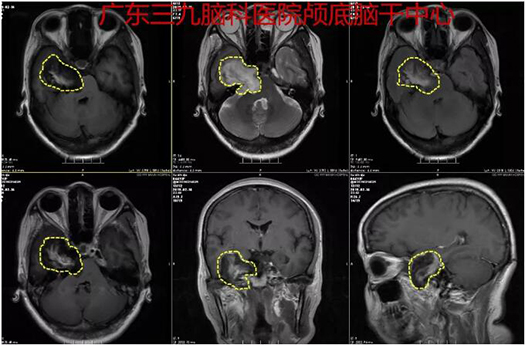

图1:术前CTA示右侧岩骨尖区跨中后颅窝占位性病变,囊壁可见钙化,病灶边缘示少许小血管影,与邻近右侧颈内动脉、双侧椎动脉V4段远端及基底动脉关系密切

图2:术前MR示右侧跨中后颅窝囊性占位性病变,综合考虑为:表皮样囊肿可能性大